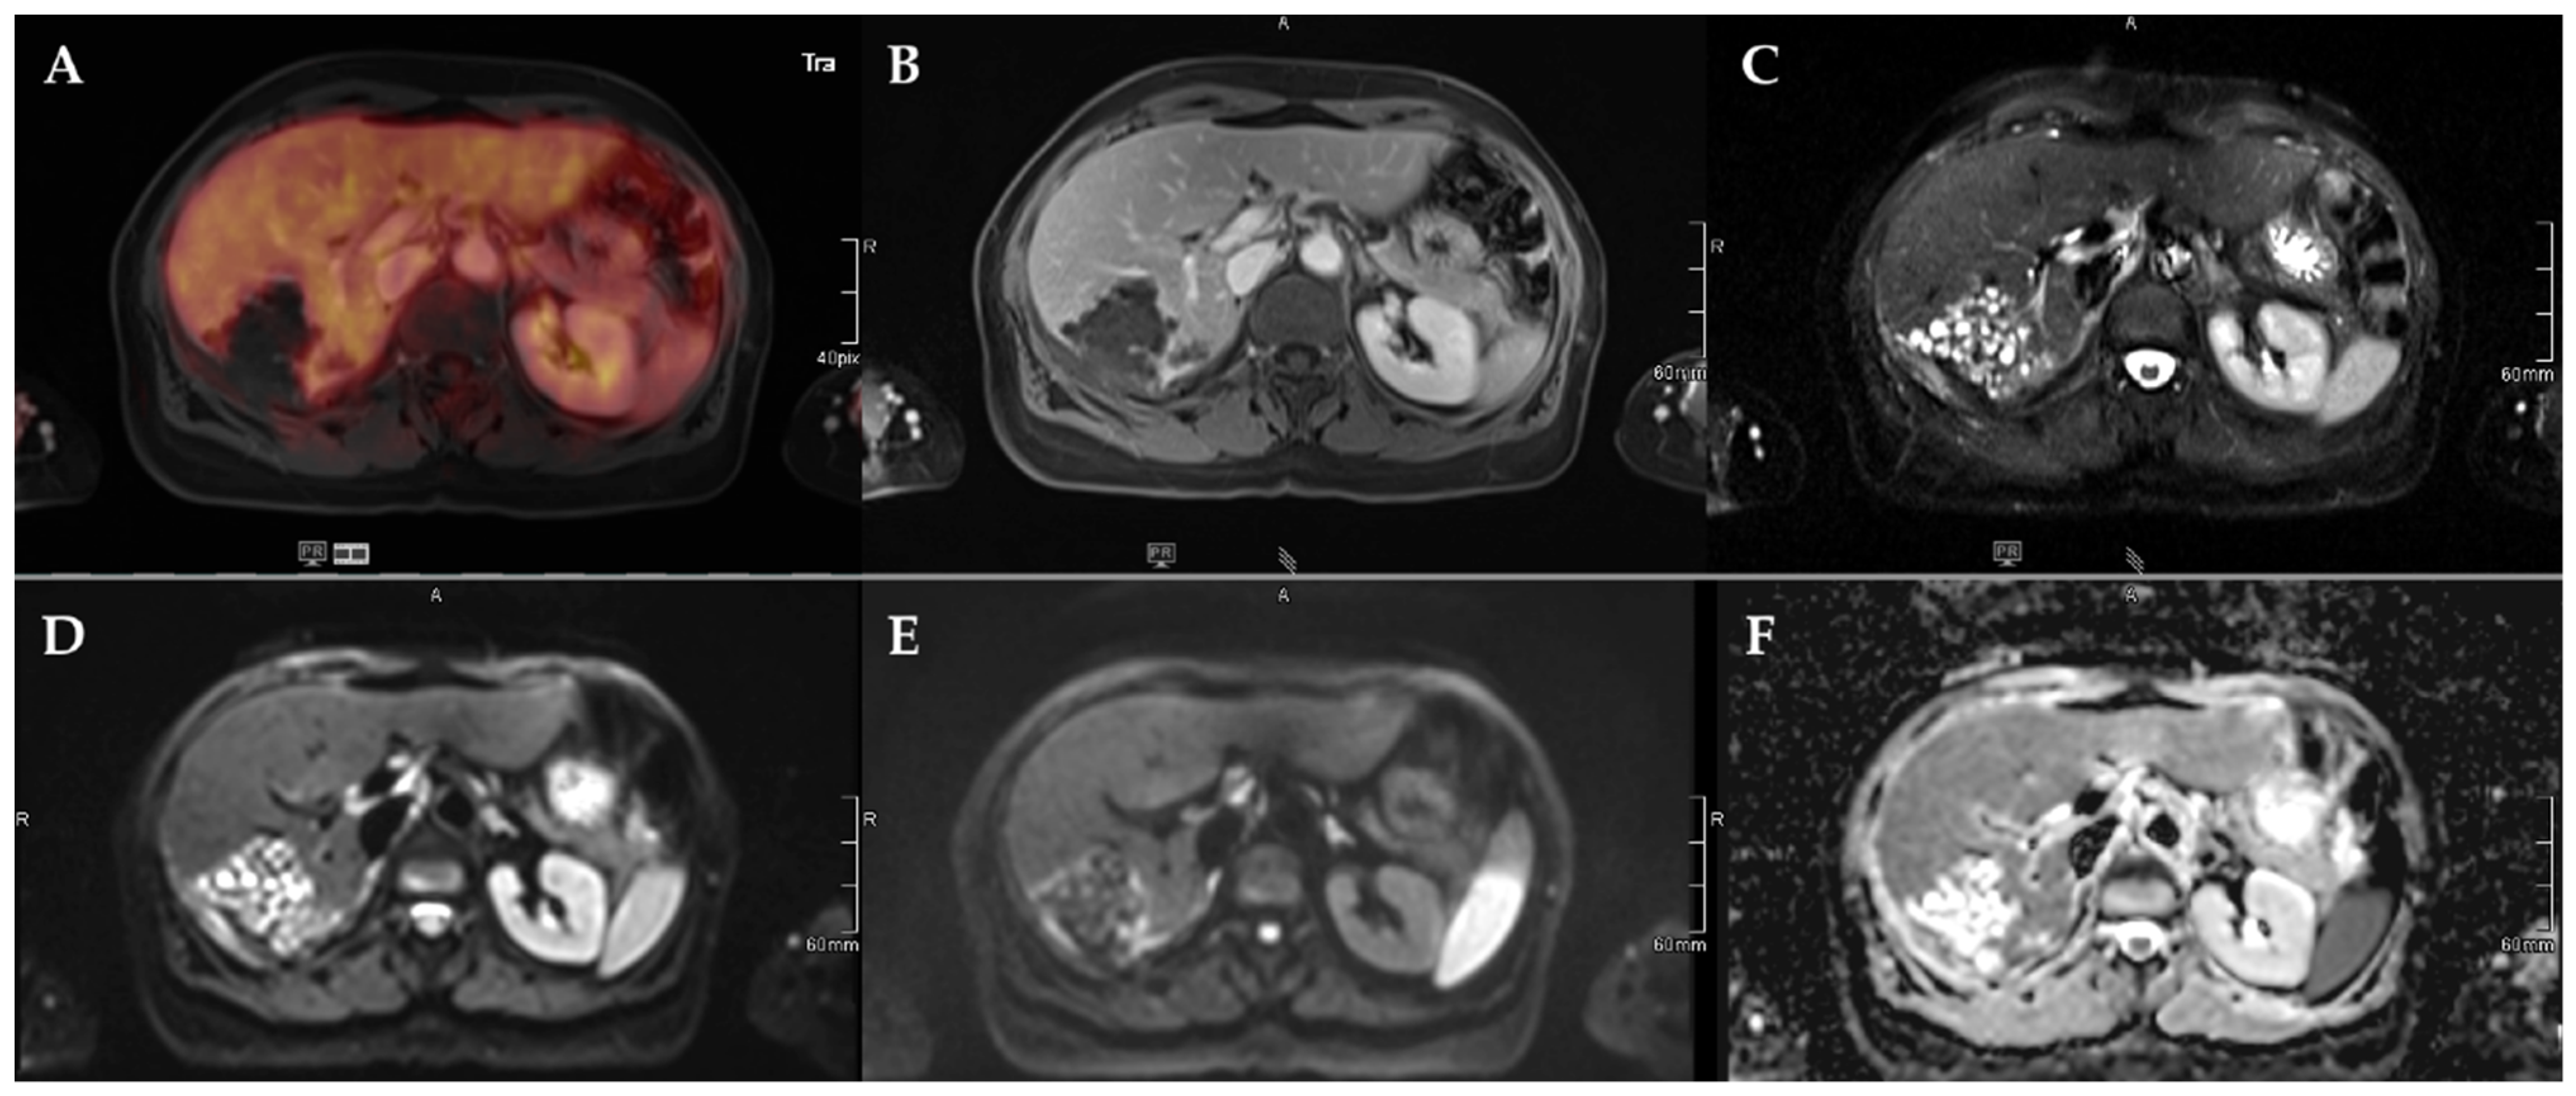

Figure 4.

72-year-old female patient with AE and a Kodama Type 1 lesion in liver segments VII and VIII. No increased FDG uptake is observed (A) and no relevant contrast enhancement (B). High signal intensity in T2w imaging with fat suppression illustrates the small cystic character of the Type 1 lesion (C). Diffusion imaging demonstrates a high signal at a low b-value (b50) in the central parts of the lesion (D), a low signal at a high b-value (b800) (E), and high ADC values (F), indicative of no diffusion restriction.